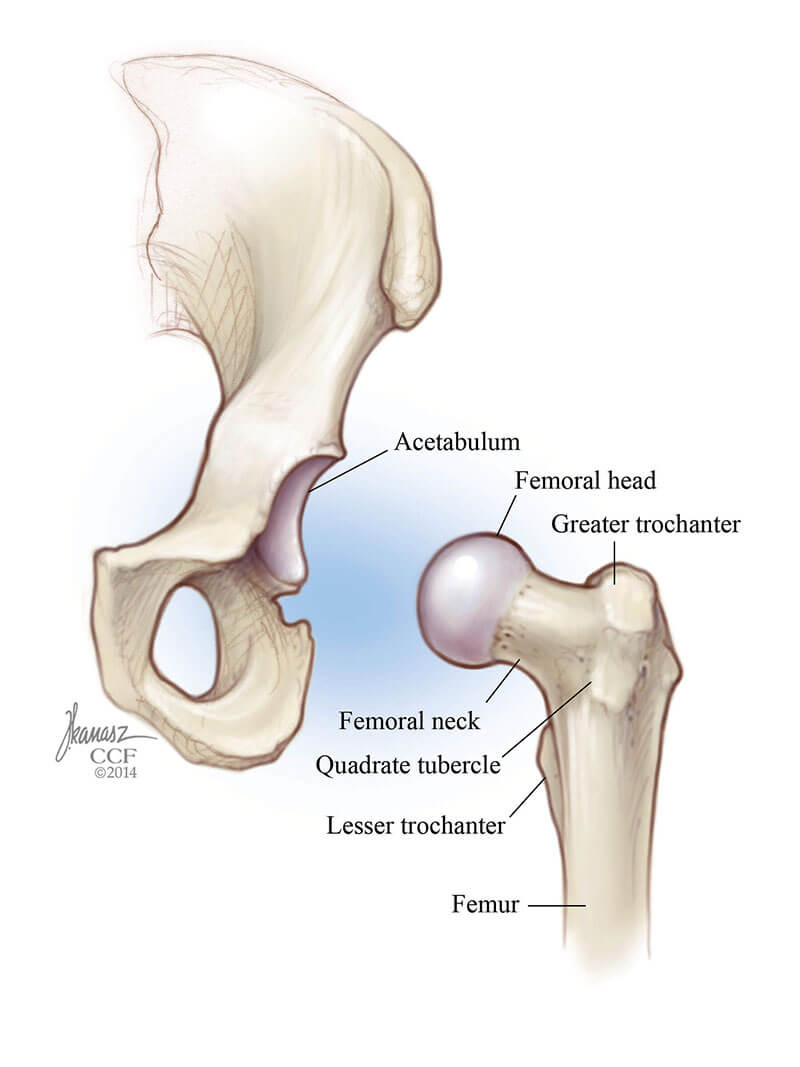

Hip problems may not be present at birth. The empty space contains the parts of the bones which. When babies are born they are examined to determine if their hips have formed normally.

Thats why your pediatrician moves your babys legs around during well-baby. The main pathology is congenital dislocation of the. An X-ray of the hip joints in children is carried out according to strict indications - only after the child reaches nine months.

The rest of your babys body will be covered to protect him or her from the x-ray beam. From the front anteroposterior view or AP from the side lateral view also known as the frog leg lateral view Typically X-rays of both hips are. Your babys developing hips will eventually make it possible for her to crawl walk climb run and even dance.

So if you look at a childs x-ray you see a lot of gaps. Babies need to be immobilized so motion doesnt affect the picture. For babies 4 months of age or older and children x-rays are performed when hip dysplasia is suspected.